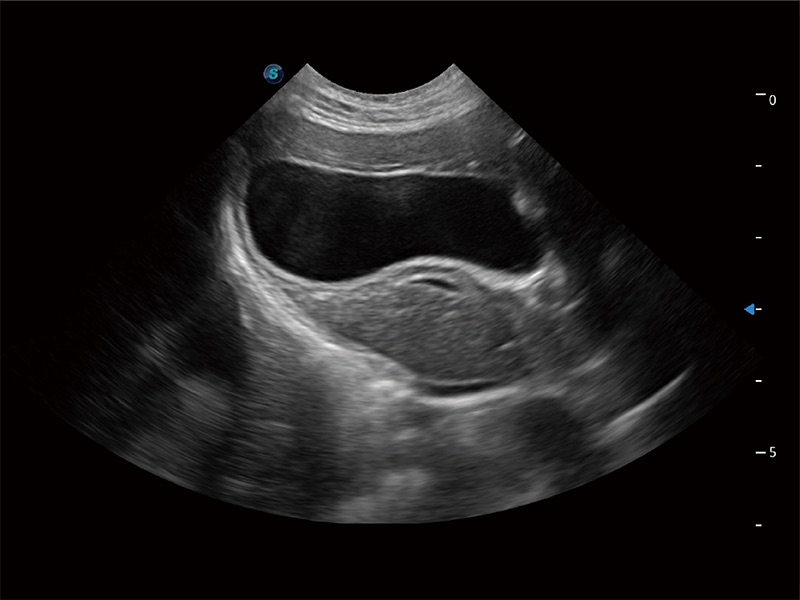

操作简便,无需高频度外力作用即可真实反映组织的形变,快速评估肿瘤良恶性。